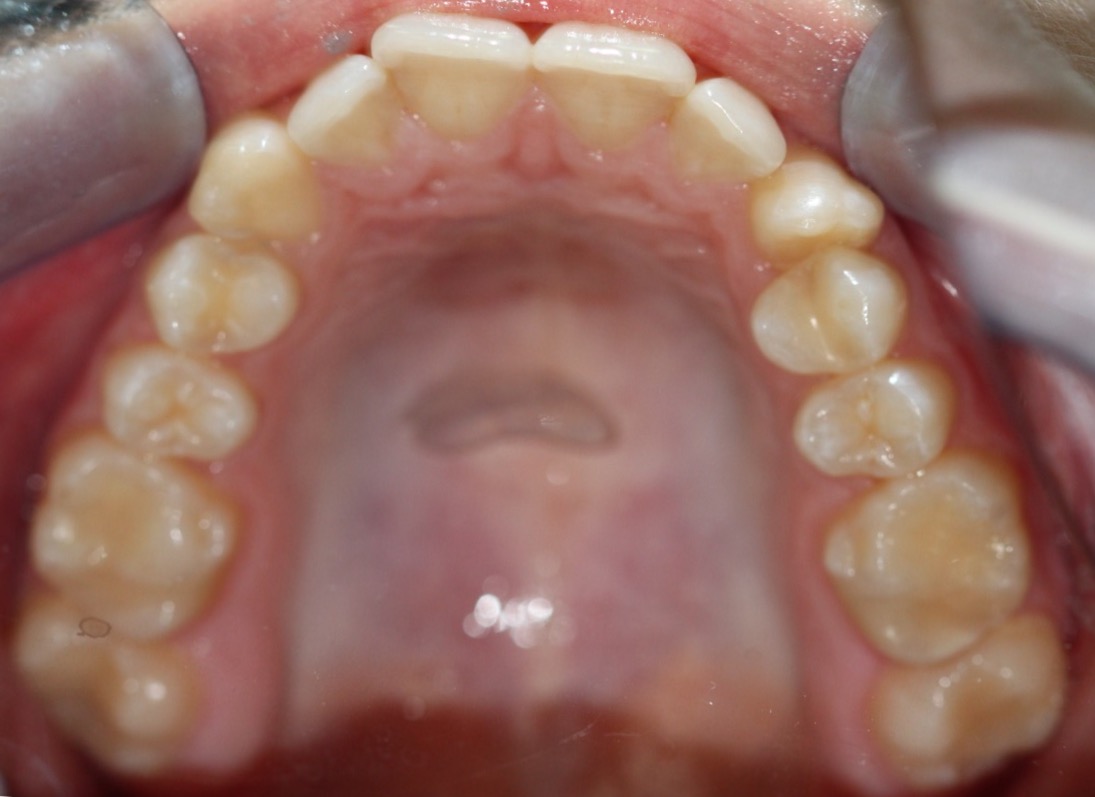

Invisalign состоит из набора индивидуальных, практически невидимых, съёмных капп(элайнеров), сменяемых 1 раз в 2 недели. Элайнеры за этот срок перемещают зубы до рассчитанного положения, после чего пациент меняет их на следующую пару.

В первый прием доктор снимает слепки с зубов пациента или делает сканирование(цифровой слепок)и отправляет их в лабораторию. Вместе со слепками или сканом доктор направляет специальную инструкцию, где подробно описывает все детали будущего лечения.

На основе этой инструкции и слепков в лаборатории создается план лечения (виртуальный 3D ролик) ClinCheck, где математически точно просчитываются степень воздействия на зубы, их направление перемещения и другие параметры. Пациент может сразу увидеть на компьютере, какой в итоге станет его улыбка и сколько по времени необходимо будет носить прозрачные каппы.